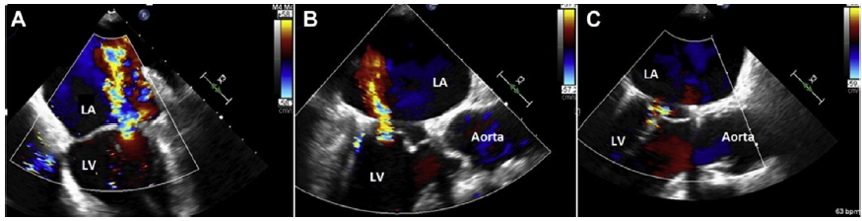

MR在心房颤动(AF)或射血分数保留的心力衰竭(HFpEF)患者中很常见,并与发病率和死亡率增加有关。众所周知,由于孤立的二尖瓣环扩张,在左心室(LV)收缩功能和几何结构正常的情况下,继发性二尖瓣返流可能存在,这种情况与房颤(AF)和射血分数保留的心力衰竭HFpEF有关,被称为心房功能性二尖瓣返流(AFMR)。这两种疾病都有共同的共病倾向,导致左心房(LA)和二尖瓣瓣环(MA)扩张,主要由左心房(LA)压力增加、拉伸和纤维化引起。这可能表明二尖瓣瓣环(MA)主要是心房结构。继发性MR是由增加的栓系力引起的,其特征可能是瓣环平面下方的一条重合线,而心房功能性二尖瓣返流(AFMR)的特征是由瓣环空间的扁平和膨胀引起的中心射流(图2),重合线位于环平面水平。

图2:二尖瓣返流(MR)的机制和分类。